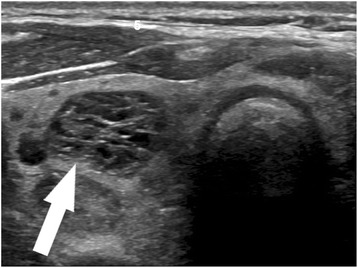

Ultrasound would be an ideal tool for prediction of indolent cancer, given that diagnosis of thyroid cancer almost always begins with sonographic evaluation of a thyroid nodule. An array of sonographic features has been used to describe thyroid nodules and identify those with features suspicious for malignancy. These features include microcalcifications, irregular borders, increased vascularity, taller-than-wide morphology, and marked hypoechogenicity (Fig. 1) [21, 22], though no single feature individually has proved to be very sensitive or specific. Conversely, a few sonographic patterns have been reliably associated with benignity in thyroid nodules, including a “spongiform” appearance (Fig. 2), an echogenic appearance in the setting of Hashimoto’s thyroiditis termed a “white knight” nodule (Fig. 3), a “giraffe skin” appearance, and a purely cystic nodule containing colloid without flow [23–25]. Elastography, a relatively new sonographic technique which assesses nodule stiffness, appears to correlate with malignancy, but further validation and wide-spread adoption will be required before stiffness measurements can be incorporated into routine thyroid nodule evaluation [26].

Fig. 1.

High suspicion pattern. Transverse grayscale sonographic image of the thyroid at level of isthmus shows a hypoechoic, irregularly marginated thyroid nodule containing microcalcifications (arrow). This is a “high suspicion” sonographic pattern in the 2015 ATA guidelines, with an estimated risk of malignancy of >70–90%. Fine-needle aspiration of this nodule showed papillary thyroid carcinoma